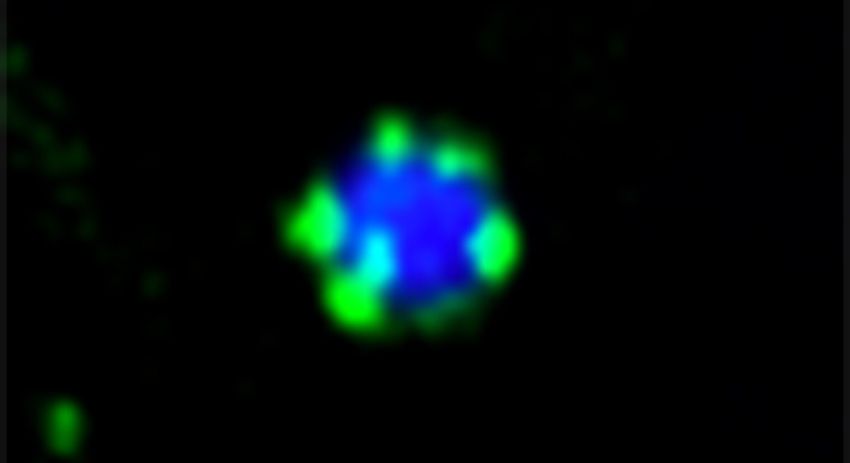

Al microscopio a fluorescenza la molecola ATG11 (verde) forma piccole goccioline sulla superficie di un aggregato proteico (blu). Fonte: Mariya Licheva / University of Freiburg

"Quando è stato raggiunto il punto di concentrazione critica, si verifica la separazione di fase: le molecole adattatrici si uniscono e formano una goccia, come olio sull'acqua", spiega Wilfling. "Un tale accumulo liquido ha proprietà fisiche diverse rispetto alle singole molecole che fungono da piattaforma flessibile per tutte le altre molecole coinvolte nell'autofagia".